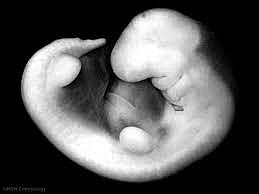

• Day 50- Secretory Phase (Stage 20)

Day 50- Secretory Phase (Stage 20)

During the 20th stage, the zygote has more of a baby appearance. One new feature during this stage is hearing.